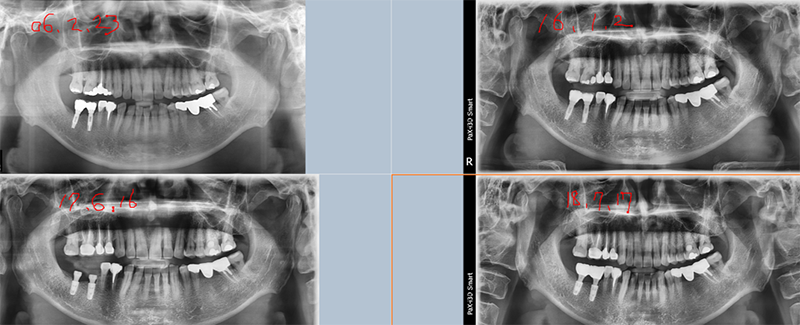

Ext. type 3.75mm Á÷°æÀÇ ÀÓÇöõÆ®.

Bruxism ÀÌ Àִ ȯÀÚ·Î½á ½É°í ±â´ÉÇÑ Áö 15³â ¸¸¿¡ ºÎ·¯Á®¼ ³»¿øÇß´Ù.

Á÷°æÀÌ 3.75mm·Î ¿¹Àü regular¿¡ ÇØ´çÇÏÁö¸¸ 4.0mmº¸´Ù ºÎ·¯Áö´Â °æ¿ì°¡ ¸¹´Ù.

¶ÇÇÑ ExtÀº º¸Ã¶ÀÌ ¿Ã¶ó°¡¸é Ç÷§Æû¿¡¼ 1.5mm °ñÈí¼ö°¡ °ÅÀÇ ÇÊ¿¬ÀûÀ¸·Î ÀϾÙ. À̹ø °æ¿ìµµ °ñÈí¼ö¿Í ±íÀº ¿¬°üÀÌ ÀÖ´Ù°í ¿©°ÜÁø´Ù.

¾Õ¿¡¼ ¾ê±âÇÑ °Íó·³ Á¦ÀÏ Áß¿äÇÑ °ÍÀº ¡°º¯ ¿¬°ñ Èí¼ö¡±°¡ ÀϾÁö ¸»¾Æ¾ß ÇÑ´Ù.